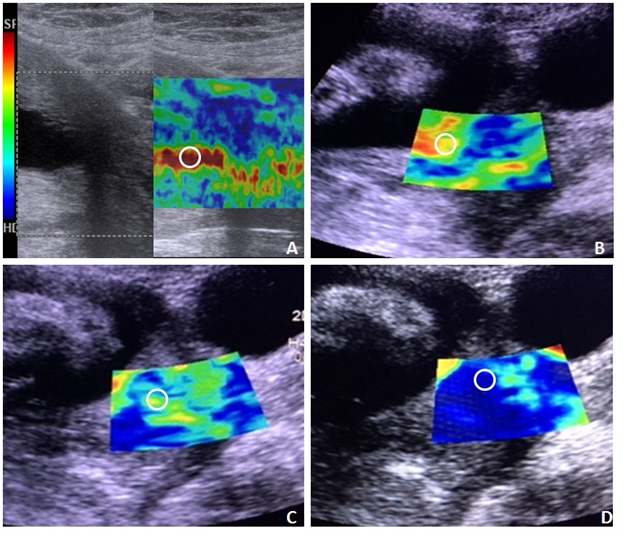

Fetal adrenal gland biometry: Fetal adrenal gland is an important but less studied subject for the prediction of the PTB. There is a cross-talk in between the fetal adrenal gland and placental endocrine pathways which are crucial for induction of labor. Fetal hypothalamic-pituitary-adrenal axis (HPA) is activated in response to fetal stress which leads to perpetuation of hormonal based signaling pathway in the form of fetal adrenal enlargement,18 secretion of fetal cortisol, more placenta mediated conversion of the sterols into estrogens, increased placental Corticotropin-Releasing Hormone (CRH) and subsequently Prostaglandins (PGE2 & PGF2α).19,20 This pathway ultimately leads to induction of premature parturition and labor, hence can be correlated with central role of Fetal adrenal gland in prediction of PTB (Figure 4).

Figure 4 Magnified view of Ultrasound images of the fetal adrenal gland, (white arrows) in all three orthogonal planes, showing measurements of the fetal zone and corresponding widest dimension. (A) both adrenal glands in transaxial plane; (B) adrenal gland length; (C) adrenal gland width and (D) adrenal gland depth in Anterio-posterior axis. Asterisk (*) shows spine in the midline.

The Fetal adrenal gland is divided into 4 zones in the fetal life from inside to outside. They are “Fetal Zone” (FZ), “Transitional Zone” (TZ), “Definitive Zone” (DZ) and finally “fetal adrenal capsule” (C).21 Activation of HPA axis leads to Fetal Zone Enlargement (FZE) and secretion of Dehydroepinadrosterone-Sulfate (DHEA-S). USG can identify the central Fetal zone as hyperechoic area and the length, width and depth of the FZ can be measured and divided by their respective widest dimensions (l/L; w/W and d/D) giving ratio or percentages of the Fetal zone. Similarly, 2D & 3D volumetric assessment of the gland is also noted and divided by the estimated fetal weight giving corrected Adrenal gland volume (cAGV, in mm3/kg).

Assessment of the fetal zone can be done in symptomatic patients for calculation of the cAGV and % of the fetal zone (likely the depth d/D; in coronal plane). The studies have found significant correlation of cAGV and d/D of the gland with increased risk of the PTB.19,22 These two parameters have been found superior to the cervical length measurement in prediction of time to delivery. Two-dimensional measurement of the depth of the adrenal fetal zone offers the potential to accurately predict PTB within 7days and is independent of the clinical signs and symptoms. The study by Turan et al.22 have given the predictive values for identification of the women at risk of PTB viz. cAGV>420mm3/kg and FZE (d/D)>49.7% which have shown 81% and 100% sensitivity respectively with corresponding >85% specificity.